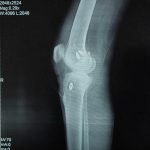

Orthopaedic Surgeon | Arthroscopy & Joint Replacement Specialist

Dr. Aditya Tripathi is a dedicated and skilled Orthopaedic Surgeon specializing in sports injuries, arthroscopy, and joint care. Known for his clinical precision, ethical practice, and patient-first approach, he focuses on helping patients regain mobility, strength, and confidence through evidence-based orthopaedic treatment. His academic background and hands-on clinical training reflect a strong foundation and a commitment to excellence in orthopaedic care.

Dr. Aditya Tripathi is widely appreciated by patients for his clear communication, honest medical guidance, and personalized treatment approach. His expertise in managing ACL tears, ligament injuries, shoulder conditions, and sports-related injuries makes him a trusted choice for comprehensive orthopaedic and sports injury care. Patients value his attention to detail, compassionate care, and focus on long-term recovery—establishing him as a reliable and respected orthopaedic specialist.

- Knee Replacement Surgery

- Fracture Treatment